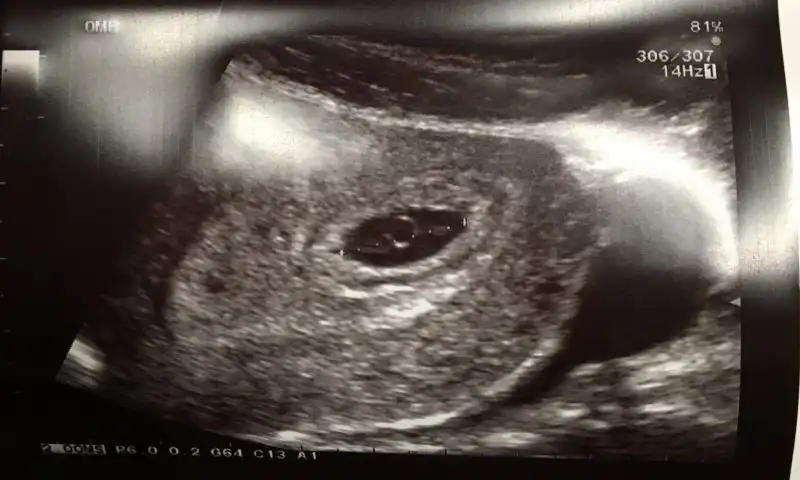

Doktorun tahminde bululnmadımıcanım sana zahmet varsa atabılırmısın tekrar kese konumu icin bu benımkıEki Görüntüle 2088211 buda 12haftalık usegEki Görüntüle 2088213

Kız gibi geldi bana ilk micanım sana zahmet varsa atabılırmısın tekrar kese konumu icin bu benımkıEki Görüntüle 2088211 buda 12haftalık usegEki Görüntüle 2088213